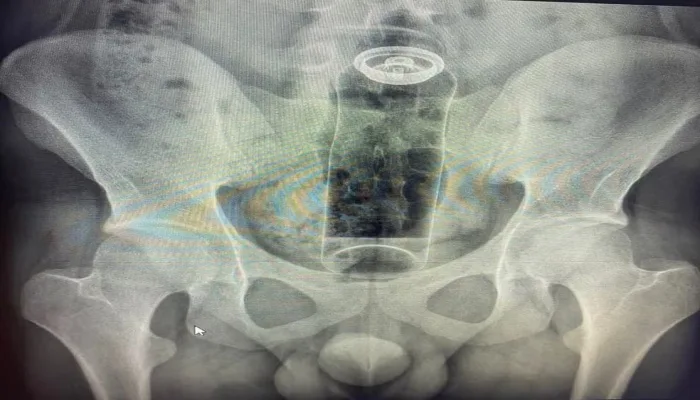

Paciente é internado após ficar com desodorante preso no reto; médicos fazem alerta

De acordo com o médico Daniel Brosco, cirurgião coloproctologista, o paciente tinha 19 anos e contou que colocou o desodorante no ânus durante uma “brincadeira” sexual. A embalagem, porém, acabou subindo para o reto e não conseguiu ser retirada em casa